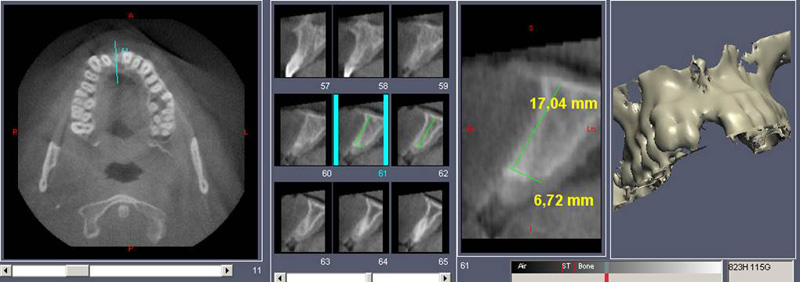

Bezzubá čelist je hlavní indikací pro ošetření pomocí implantátů. Zejména celkové zubní náhrady v dolní čelisti mají velice nízkou stabilitu a držení díky velkému úbytku kosti.

S pomocí zubních implantátů můžeme díky různým kotevním systémům (třmeny, kulové hlavy, Locatory) zajistit stabilitu a držení protézy nebo při použití většího počtu implantátů zhotovit pevné náhrady – můstky nalepené nebo našroubované na pevno na implantáty.

S těmito typy náhrad můžeme dosáhnout perfektní funkci, výbornou estetiku, fonetiku a současně zajistit u pacienta možnost dobré hygienickou péče a čištění, která je pro životnost implantátů velice důležitá.